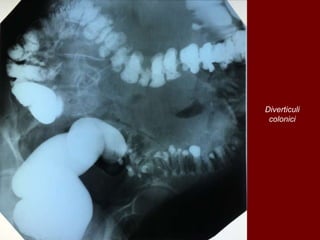

Diverticuli

colonici